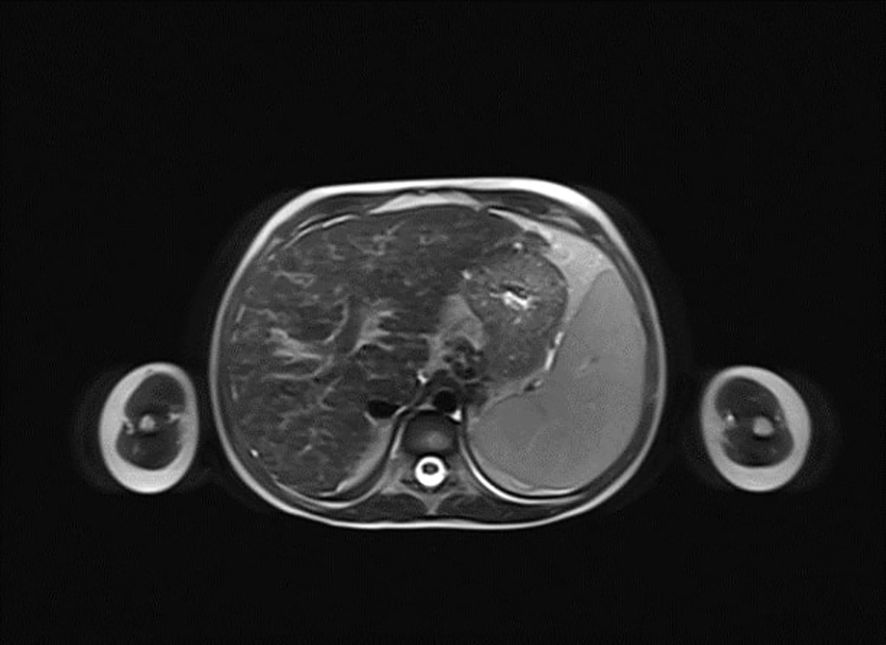

A 6-year-old girl was admitted to the Department of Pediatrics, Endocrinology, Diabetes with the Cardiology Division due to suspected diabetes mellitus. The parents reported a 4-day history of polyuria and polydipsia, along with a persistent acetone-like breath odor lasting two weeks after a respiratory infection. They did not observe any other concerning symptoms. According to the parents, the patient had no significant prior health issues, was not on any chronic medications, and had no known allergies. The family history was negative for diabetes mellitus. On admission to the Department, the general condition was good, with stable circulatory and respiratory function, logical contact, blood pressure of 91/48 mmHg, and a heart rate of 120 beats per minute (bpm). Physical examination revealed dry oral mucous membranes, a tongue coated with a white film, petechiae on the upper limbs, a distended abdomen, arched above the chest level, and increased bowel sounds. Laboratory findings showed significant abnormalities, including hyperglycemia (578 mg/dL), hyponatremia (128 mmol/L), hypochloremia (93 mmol/L), increased glycated hemoglobin fraction A1c (HbA1c; 9,29%), elevated liver enzyme levels, in gasometry features of compensated metabolic acidosis (pH = 7.38, HCO3 = 14.3 mmol/L, base excess [BE] = −9.8). Urinalysis revealed ketonuria (+++) and glucosuria (+++). Peripheral blood counts demonstrated pancytopenia confirmed on two occasions, with white blood cell counts dropping from 3.78 to 1.9 ×109/L, hemoglobin levels from 7.2 to 4 g/dL, and platelet counts from 35,000 to 22,000/μL. Laboratory findings showed coagulation abnormalities, including extended prothrombin time (PT) and activated partial thromboplastin time (APTT), reduced fibrinogen levels, and increased D-dimer concentrations. Diabetes mellitus and diabetic ketoacidosis were diagnosed. The performed additional laboratory tests revealed autoimmune markers for diabetes mellitus type 1, including anti-islet cell antibodies (ICA) at 160 Juvenile Diabetes Foundation (JDF) units and anti-glutamic acid decarboxylase autoantibodies (GADA) at 1779.41 U/mL. Hence, diabetes mellitus type 1 was diagnosed. The treatment included insulin therapy and intravenous electrolyte supplementation, achieving normalization of glycemia and improvement of gasometric values. Subcutaneous insulin therapy and a diabetic diet were initiated on the second day of hospitalization. Abdominal ultrasound revealed mild hepatomegaly and splenomegaly measuring 116 mm. Chest X-ray showed no significant abnormalities. Because of persistent pancytopenia, an oncohematology consultation was conducted. The patient received transfusions of irradiated leukocyte-depleted platelet concentrate and irradiated leukocyte-depleted red blood cell concentrate. Bone marrow biopsy did not indicate a proliferative process but indicated reactive changes. Testing for parvovirus B19 DNA in the bone marrow was negative. Celiac disease was confirmed by highly elevated titers of anti-tissue transglutaminase (tTG) antibodies, anti-deamidated gliadin peptide (DGP) antibodies, and anti-endomysial antibodies (EMA), results exceeded the upper limit of normal by 10-fold. A gluten-free diet was initiated. Microbiological diagnostics, including molecular testing, showed no evidence of active infection. Serological studies demonstrated slightly elevated anti-Epstein-Barr virus (EBV) antibodies in the immunoglobulin (Ig) M (IgM) class and significantly elevated IgG antibodies, along with low anti-severe acute respiratory syndrome coronavirus 2 (SARS-CoV-2) antibody levels. Respiratory antigen testing detected the presence of Haemophilus influenzae. The levels of lactate dehydrogenase (LDH) and uric acid were within normal limits. Echocardiography of the heart and thyroid ultrasound showed no abnormalities. Follow-up biochemical tests revealed elevated aminotransferase activity, increased bilirubin levels, decreased albumin levels with normal total protein levels, and slightly elevated ammonia levels. Coagulation assessment showed persistent hypofibrinogenemia, elevated D-dimer levels, and prolonged PT and APTT. Reduced activity of clotting factors VII, IX, XI, XII, and protein C was observed. Following gastroenterological, hematological, and immunological consultations, diagnostics were expanded to include an antinuclear antibody (ANA) panel, which yielded negative results. A significant decrease in complement components 3 (C3) and 4 (C4), elevated levels of IgG (32 g/L) and IgA, normal IgM levels, and normal IgG4 subclass levels were observed, along with lymphopenia in flow cytometry. Subpopulation analysis revealed decreased T lymphocyte counts, including cytotoxic T cells and NK cells, and a reduced percentage of memory T cells. Evaluation of T-cell maturation showed normal percentages of recent thymic emigrants (RTE) and regulatory T cells. B-cell maturation assessment revealed a slightly reduced percentage of switched memory B cells and an increased percentage of IgM-only memory B cells. The percentage of double-negative T cells (DNTC) was slightly elevated. Based on these results, intracellular perforin expression disorders and common humoral and cellular immune deficiencies, as well as complement component deficiencies, were excluded. A panel-based genetic study was ordered to investigate genes whose defects lead to primary immunodeficiency disorders (Additional file 3). Next-generation sequencing (NGS) was performed using the custom-designed SureSelect XT2 Panel (Agilent Technologies, Santa Clara, CA, USA), in a range of genes related to inborn errors of immunity. Sequencing libraries were prepared according to the manufacturer’s protocol and set on the NextSeq 550 platform in the process of a 300-base-pairs (bp) paired-end run (Illumina, San Diego, CA, USA). The data analyses of the target regions were performed using Burrows-Wheeler Aligner Genome Alignment Software and the GATK Variant Caller algorithms and mapped to the human genome reference sequence GRCh37/hg19. The results were next analyzed using Variant Studio v.3.0 (Illumina), SureCall v.4.1 (Agilent Technologies), and Integrative Genomics Viewer v.2.3. The filtering criteria included coverage with at least 20 reads and a minor allele frequency (MAF) below 0.01 in the GnomAD database. Bioinformatic predictions were conducted using the Mutation Taster, SIFT, and PolyPhen platforms. The pathogenicity was determined according to the American College of Medical Genetics (ACMG) classification rules. The analysis did not identify any pathogenic or potentially pathogenic variants. In the anti-tissue antibody panel, positive anti-smooth muscle antibodies (ASMA) and a strongly positive result for anti-liver cytosol antigen type 1 (LC1) antibodies were detected. Differential diagnosis excluded hepatitis A, hepatitis B, hepatitis C, alpha-1 antitrypsin deficiency, and Wilson’s disease, with serum ceruloplasmin levels and urinary copper excretion within normal ranges. IgG4 levels were within normal limits. Urinary bile acid analysis via gas chromatography-mass spectrometry (GC-MS) ruled out inherited metabolic defects. Abdominal Doppler ultrasound excluded portal system thrombosis and revealed a nodular liver with increased stiffness and signs of portal hypertension. Elastography using the S-Shearwave method yielded a METAVIR fibrosis stage F4 – 54.2 kPa, with an interquartile range (IQR) of 18.7%. Gastroscopy excluded esophageal varices and revealed macroscopic changes typical of celiac disease. Magnetic resonance cholangiopancreatography (MRCP) confirmed micronodular cirrhosis with moderate biliary changes (Figures 1, 2). Based on the overall clinical picture and additional test results – significantly elevated alanine transaminase (ALT), hypergammaglobulinemia, high IgG levels, presence of autoantibodies, and exclusion of other causes of chronic liver pathology – autoimmune hepatitis was diagnosed. In the following year, the diagnosis was confirmed by a core needle liver biopsy performed at the Children’s Memorial Health Institute (CMHI). Platelet-bound IgG and IgM on platelets were detected using the direct immunofluorescence (DIF) test. This test, combined with the earlier exclusion of other possible causes of low platelet count, led to the diagnosis of immune thrombocytopenia. Consequently, the patient was diagnosed with a multi-organ autoimmune disease (APS-4; diabetes mellitus type 1, celiac disease, immune thrombocytopenia, autoimmune hepatitis with cirrhosis; Table 1).

Figure 2

MRI scan of the abdomen showing a transverse section. The image displays liver tissue with varying shades of gray representing different densities. Darker areas may suggest denser tissue. Light and dark patterns are present, indicating normal and abnormal structures.

Figure 2. Horizontal plane image from magnetic resonance cholangiopancreatography (MRCP) presenting micronodular cirrhosis with moderate biliary changes.